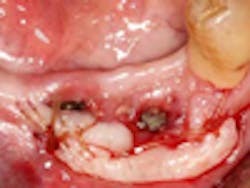

The free gingival graft (FGG) (Fig. 1) is an age-old periodontal procedure first described by Sullivan & Atkins in 1968. (9) It has long been the gold standard for increasing attached gingiva around the natural dentition. Connective tissue grafting (CTG) (Fig. 2) provides many of the same benefits along with root coverage, without the accompanying discomfort from the donor site, making the FGG less desirable. However, the FGG procedure has its advantages over CTG for both the natural dentition and, more recently, dental implants.